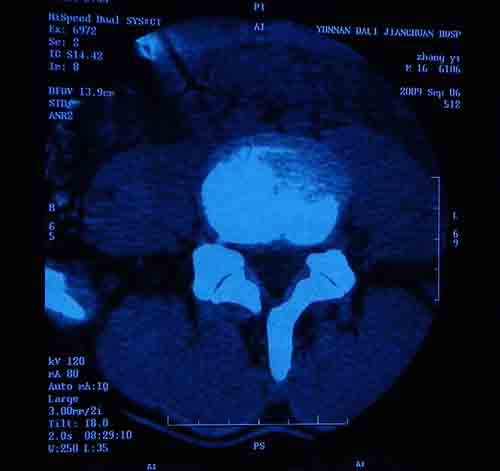

标题: CT22052:腰5/骶1椎间膨突出外,还有点异常,不知是什么东东 [打印本页]

标题: CT22052:腰5/骶1椎间膨突出外,还有点异常,不知是什么东东

腰5/骶1椎间膨突出外,还有点异常,不知是什么东东,请各位大虾帮忙看看(12骨窗最明显)

椎体后缘软骨结节